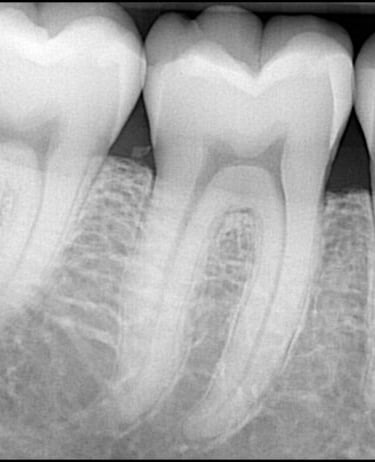

Intraorálne röntgenové snímky sú ako malý detektív, ktorý sa pozerá do miest, ktoré oko nevidí. Tento typ röntgenového snímku sa robí priamo v ústach a ponúka detailný pohľad na jednotlivé zuby a ich okolie. Intraorálne röntgenové snímky sú rýchle a jednoduché, často trvajú len niekoľko sekúnd, a vďaka ich presnosti sa zubný lekár môže zamerať na problémové miesta a liečiť ich skôr, ako začnú spôsobovať bolesť alebo väčšie problémy.